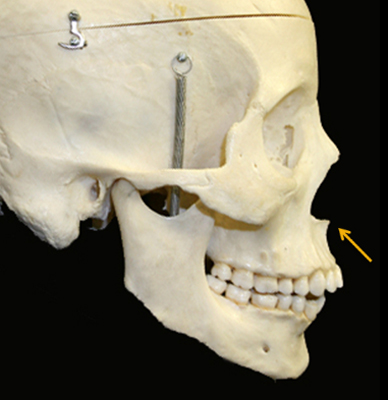

What is the anterior nasal spine?

The ANS is the small bone that sticks out at the very base of your nose, between the nostrils:

Seen from the front:

The ANS is the small bone that sticks out at the very base of your nose, between the nostrils:

Seen from the front: